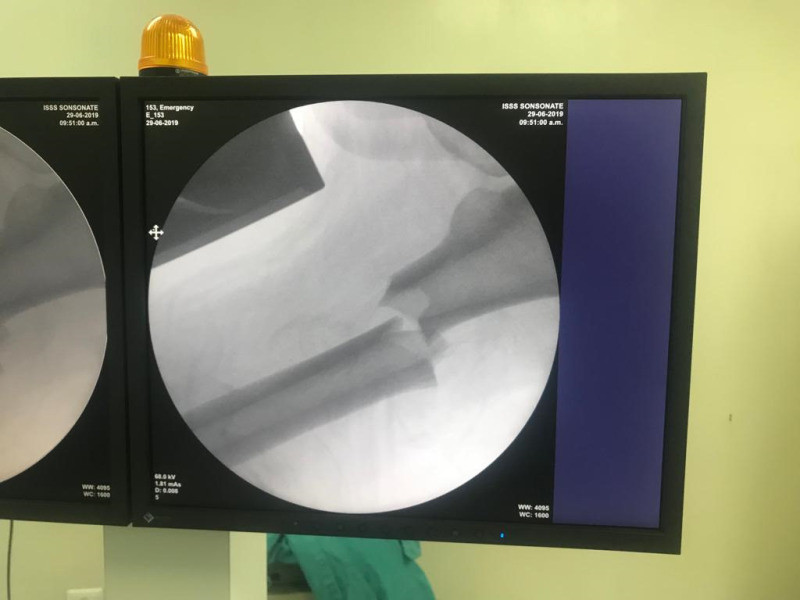

Imágenes de ortopedia y traumatología

Envíado por Dr. José Israel Flores Hernández